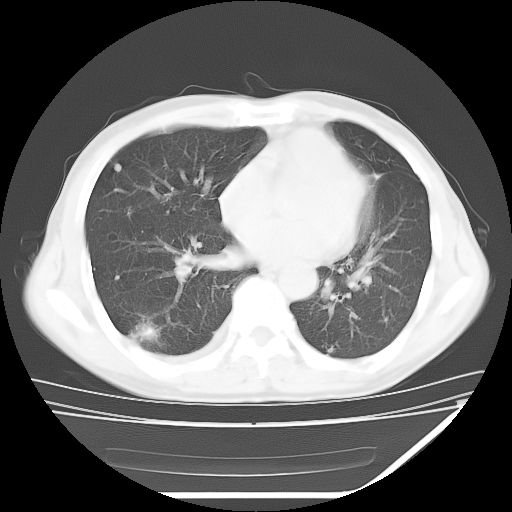

男,59岁,“结核性胸膜炎”30余年,胸部经常疼痛,多次x检查提示“肺部”炎症。腹部疼痛5日,b超提示:“肝内短管结石,余显示不清,建议进一步检查。”

两肺结核并右侧胸腔积液;脾脏、腹腔及腹膜后淋巴结结核[陈旧性];肝内胆管结石

胸部腹部都是结核(双肺。纵隔淋巴结,肝脏,脾脏,肠系膜)